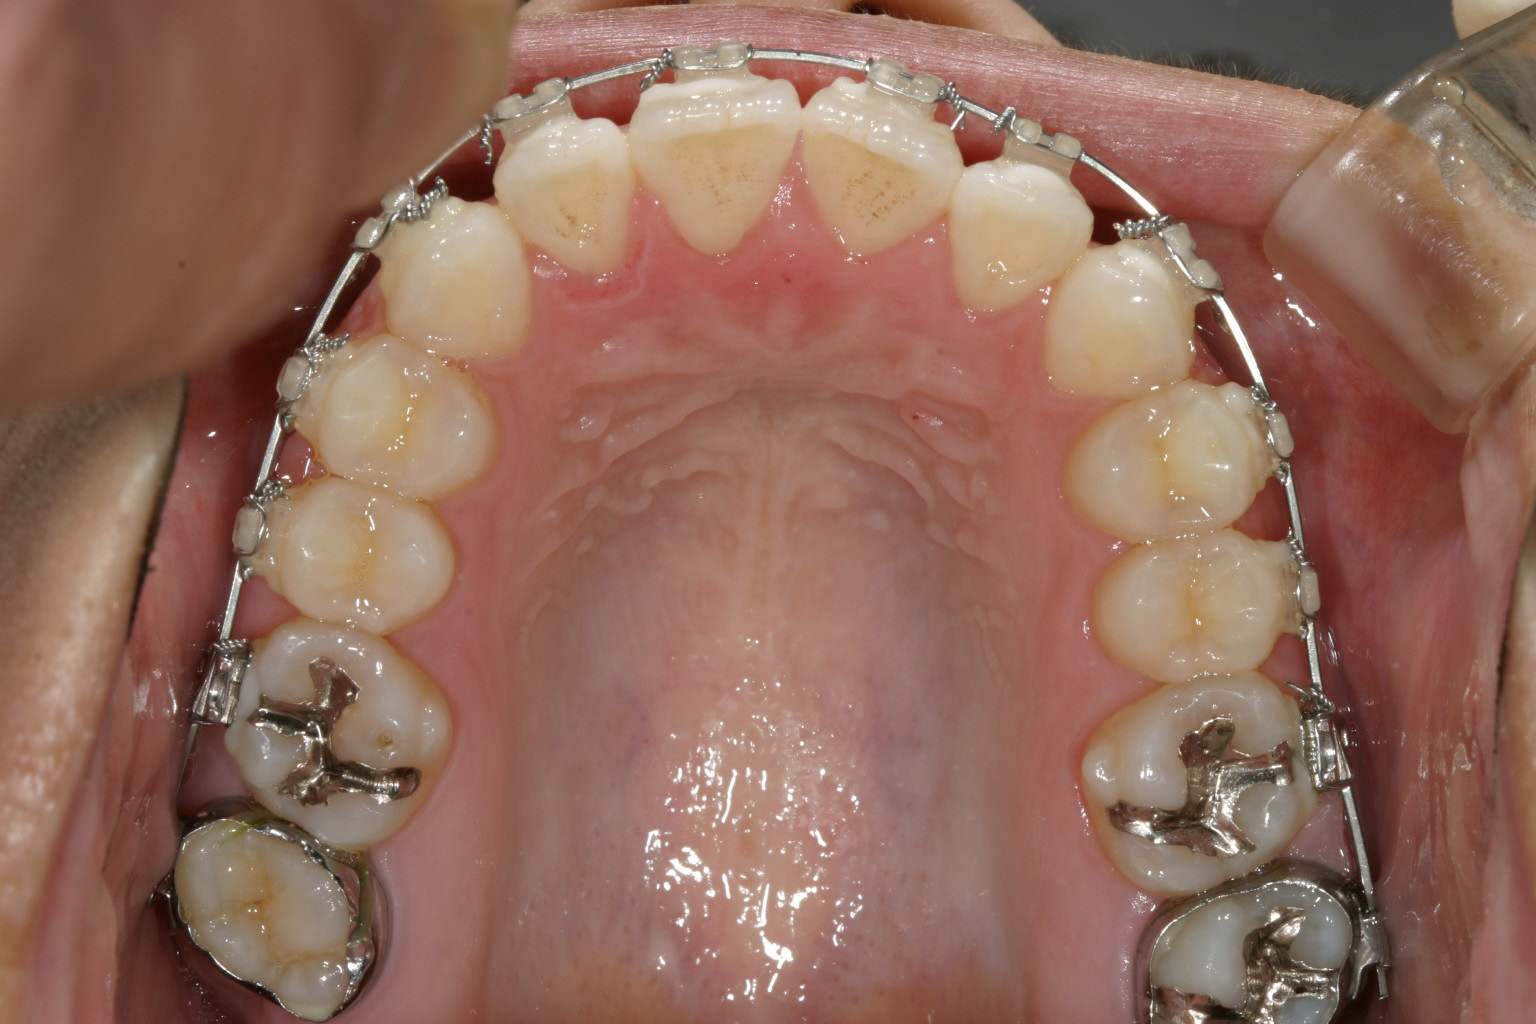

治療開始から半年後です。 犬歯間も広がり綺麗に並んできました。

綺麗に改善しました。

全体的にアーチが尖ったV字歯列をされてましたのでU字に改善させ、また臼歯部を圧下させる方法により前歯を咬合させました。